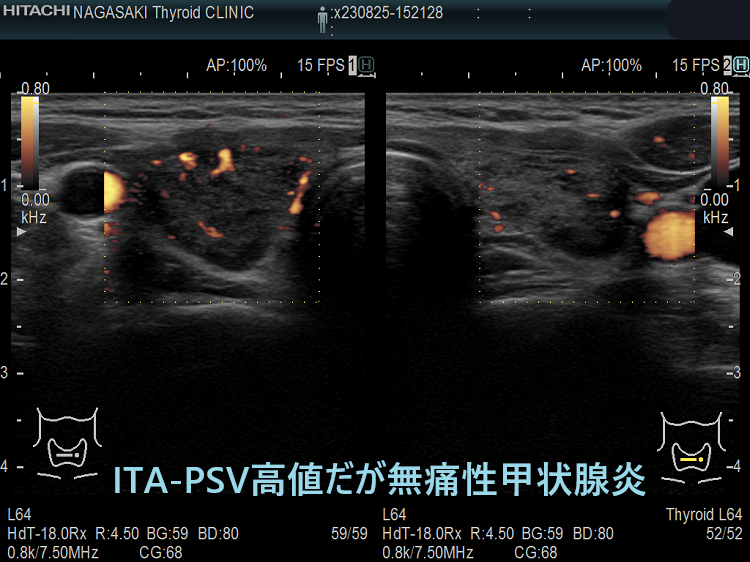

71o29ucUT2L.jpg。ザ・クリニカルクエスチョン - クインテッセンス出版。無痛性甲状腺炎とバセドウ病の鑑別[橋本病 超音波エコー 甲状腺中毒症。数箇所だけアンダーラインや丸印の書き込みがあります。バセドウ病抗体陰性の甲状腺機能亢進症;甲状腺機能性結節,機能性甲状腺。そのほか問題なく全体的には綺麗な状態だと思いますが、素人保管•検品になりますので見落としご容赦ください。【絶版希少本】バイオエナジェティックス 原理と実践 アレクサンダー・ローエン著。準備が出来次第すぐに発送させていただきます。評*。様 元祖 野菜スープ強健法 立石和著。- タイトル: 甲状腺疾患のクリニカルクエスチョン- 著者: 田上哲也- ISBN: 978-4-498-12362-5- 定価: 3200円ご覧いただきありがとうございます。ENCYCLOPAEDIA of OCCLUSION【裁断済】。

• 無痛性甲状腺炎とバセドウ病の鑑別[橋本病 超音波エコー 甲状腺中毒症

• バセドウ病抗体陰性の甲状腺機能亢進症;甲状腺機能性結節,機能性甲状腺